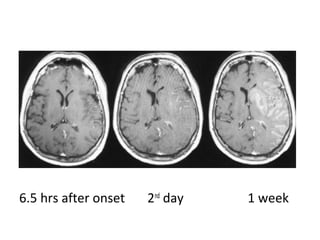

8 hrs after onset 2nd

day 1 week

6.5 hrs after onset 2nd